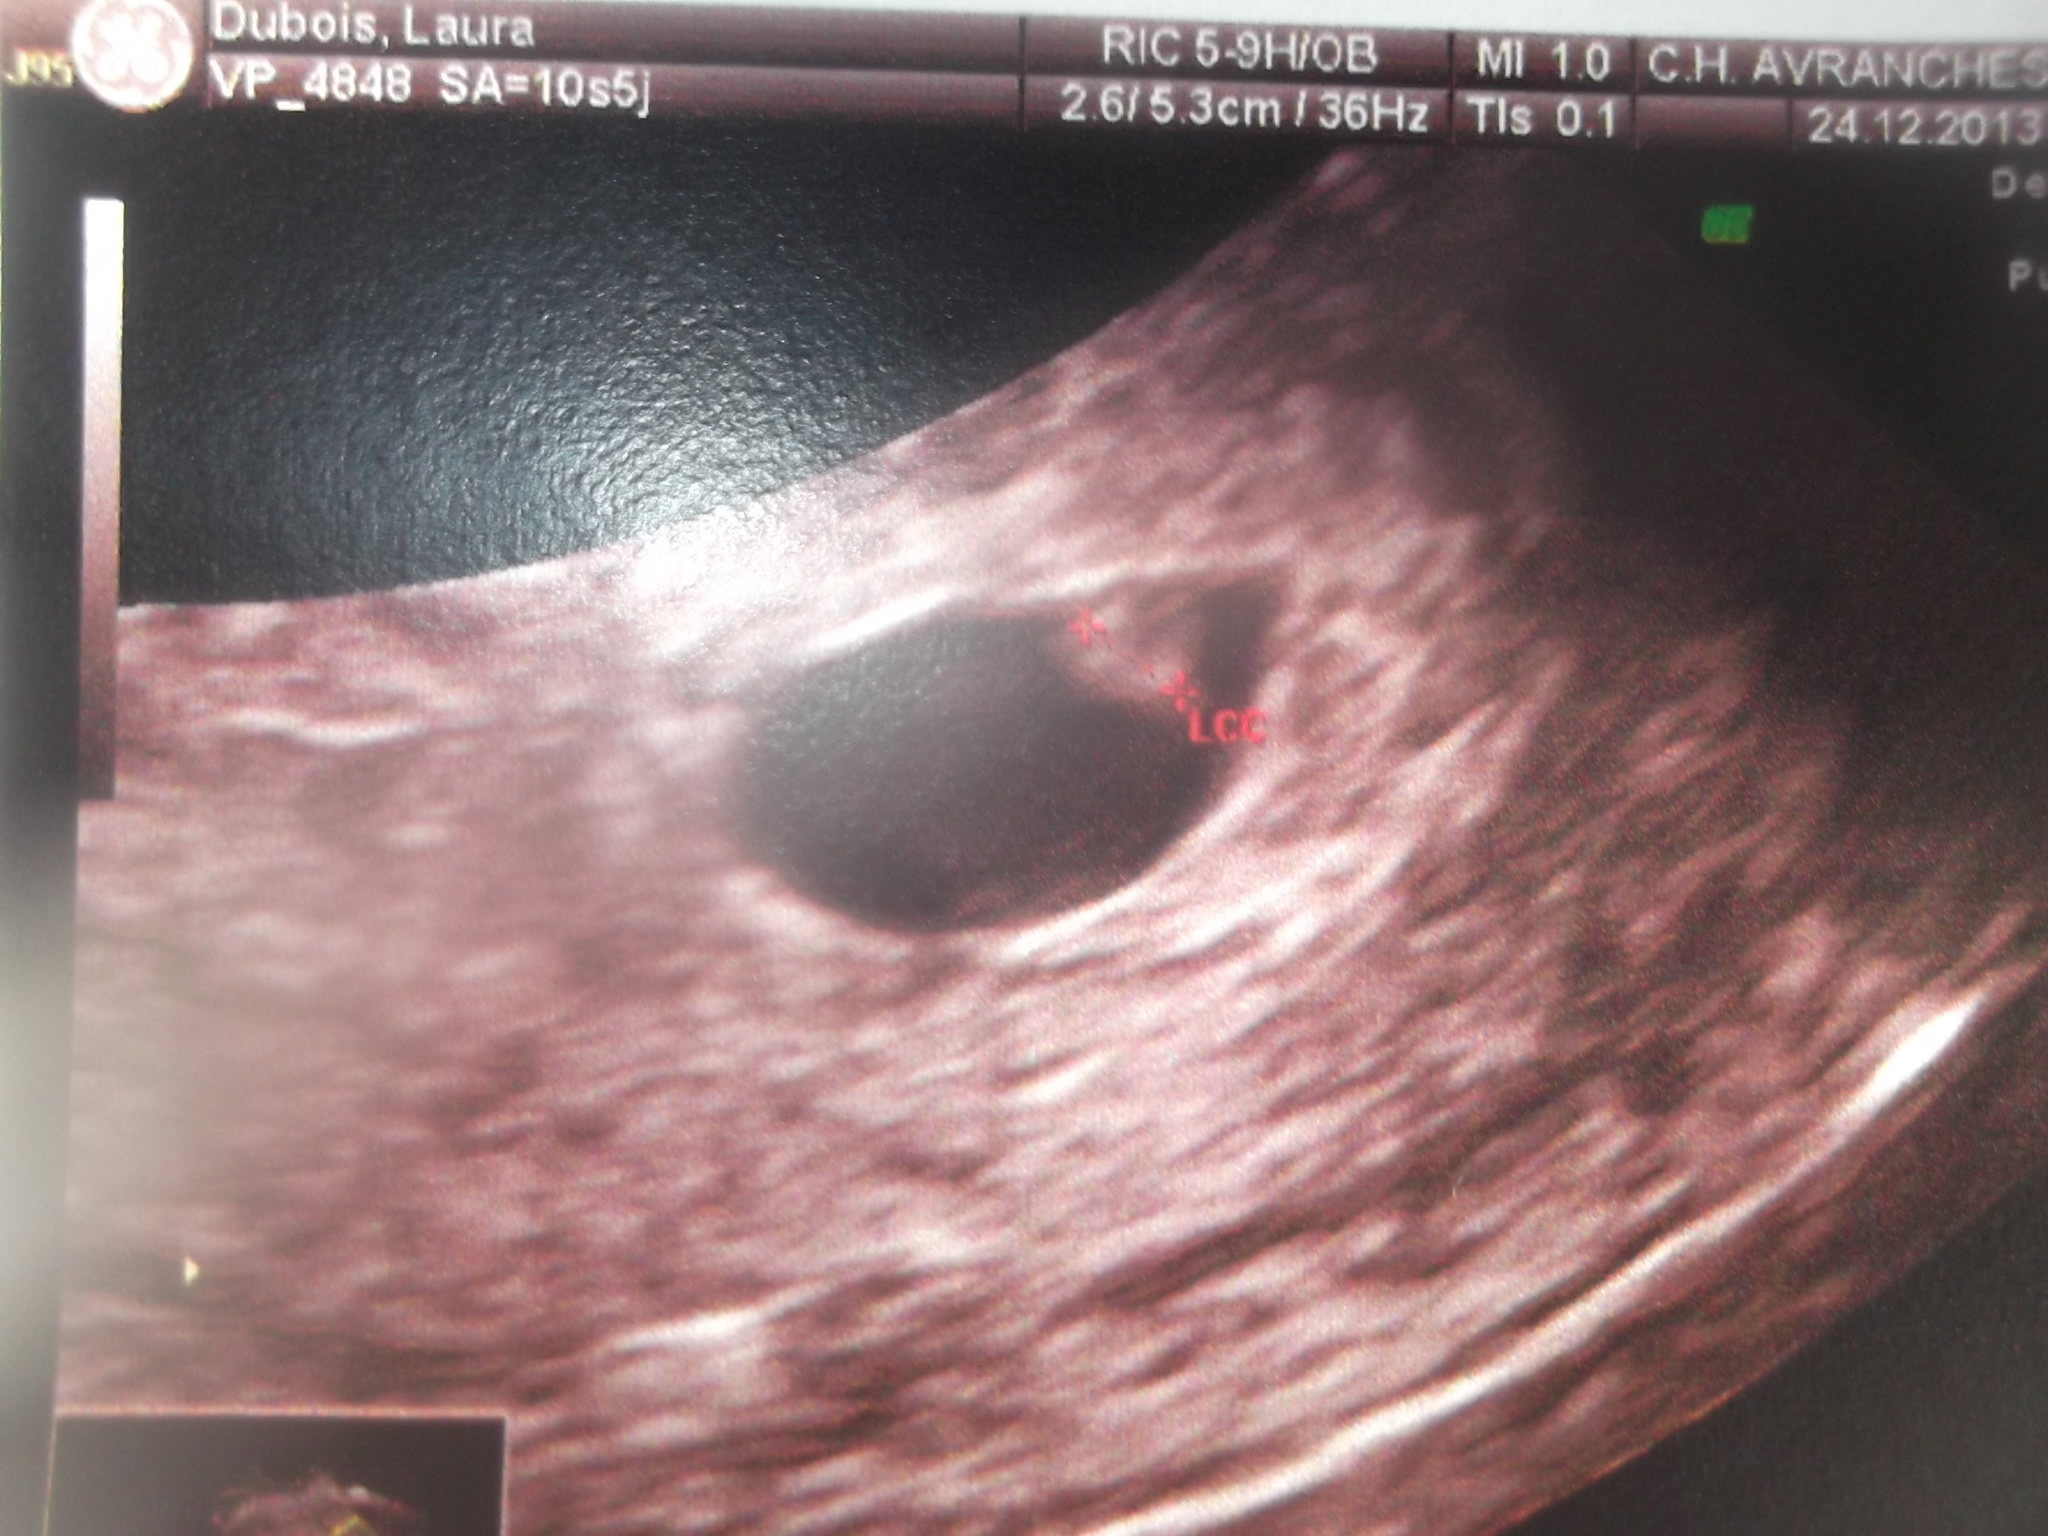

voila se que je peut te montrer et apparemnt je sui a 6sa

c'est le sac de grossesse qui mesure 12.9 mm et ce qui est dedant 2.5 mm